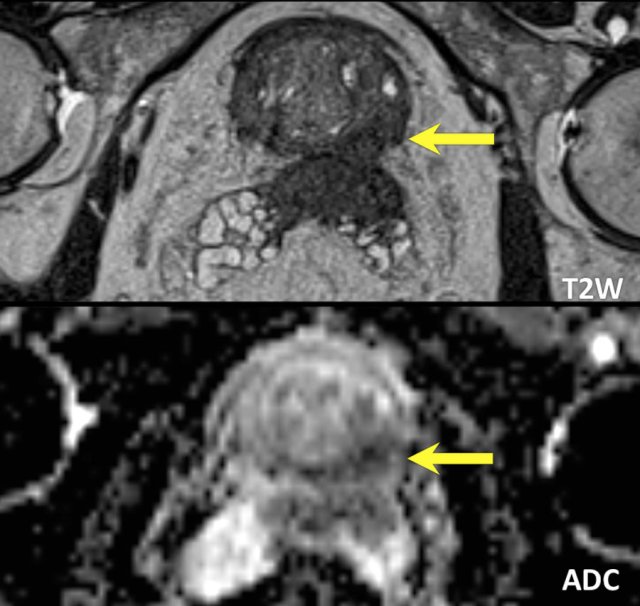

Benign prostate hyperplasia

Benign prostate hyperplasia (BPH) results in the formation of well-circumscribed, encapsulated nodules in the transition zone.

Some of these nodules have dense stroma with low T2W signal intensity and low ADC (yellow arrow).

The most important characteristic feature to distinguish BPH nodules from malignancy is the generally well-defined and well-circumscribed morphology interpreted in axial, coronal and sagittal series.

The left peripheral zone lesion was classified as PI-RADS 5 (red arrow).

MRI- targeted biopsy revealed a Gleason 3+4.

T2 hypointense BPH nodules can be less distinctly circumscribed within the transition zone and may show some degree of restricted diffusion.

Also, these nodules tend to enhance early and intensely on DCE, making conclusive characterization difficult.